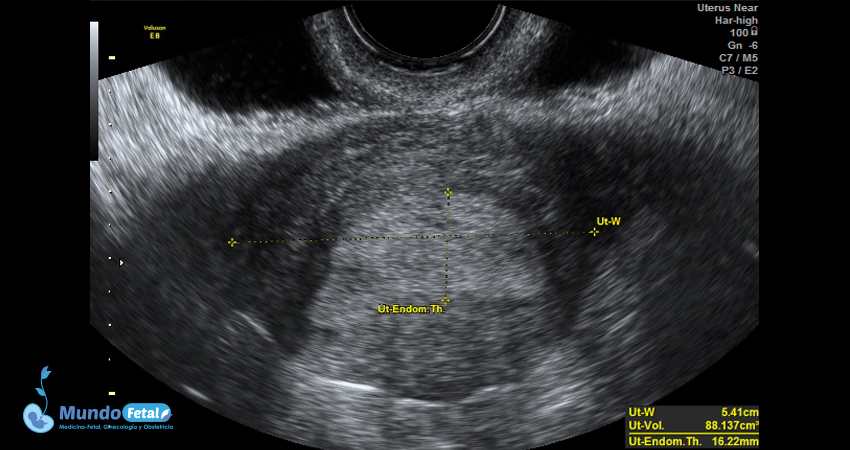

Ultrasonido Pélvico

Estudio anatómico de la región pélvica, que brinda información precisa de (vagina, cérvix, útero, endometrio, trompas de Falopio, ovarios y sus tejidos anexos) de cada uno, descartando alguna complicación de estas estructuras.